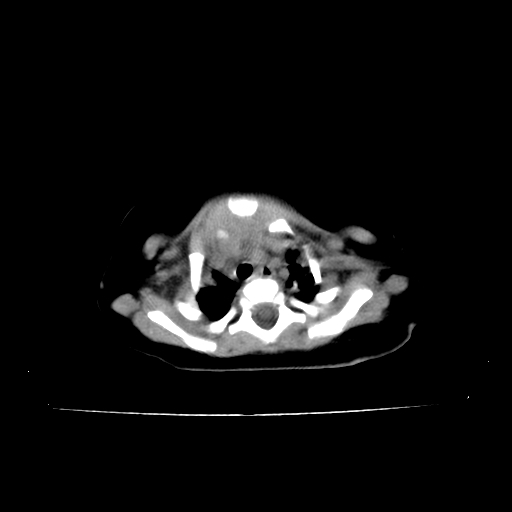

以下是引用影像之路在2009-5-8 15:46:00的发言:[br]1)胸廓畸形。2)考虑两肺感染性病变,并右肺上中叶肺不张;建议抗炎治疗后复查。3)胸腺肥大。4)前上中纵隔占位性病变待排;建议追踪复查。

以下是引用余辉在2009-5-8 8:44:00的发言:[br]鸡胸,胸腺肥大,双肺感染性病变,结合病史支原体肺炎可能性大